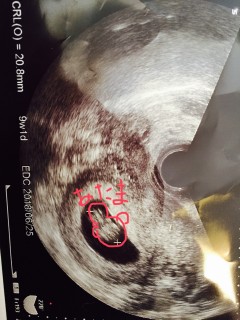

2週間前はまだ不安定な心拍だったけど、今回はしっかり心拍取れて予定日も決まりました◎ 大きさは20.5mmで平均くらいだそうです◎ うれしい! これから一緒に頑張ろうね☆